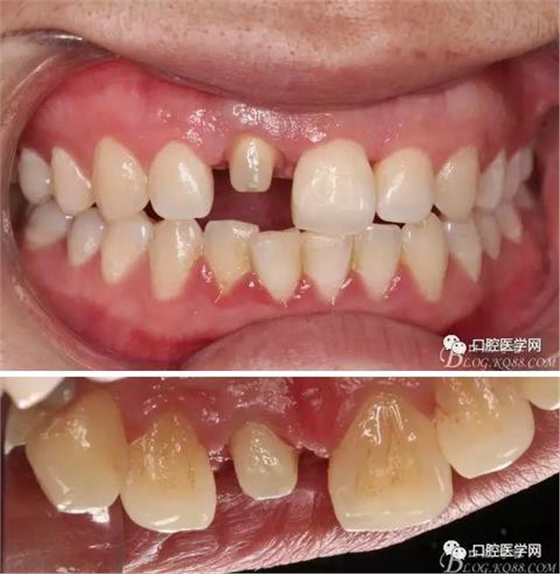

術(shù)前口內(nèi)照,11殘根,唇側(cè)牙齦紅腫,肩臺在齦下2毫米,舌側(cè)正常.21有被動萌出,長寬比例不協(xié)調(diào)??谇恍l(wèi)生一般,有菌斑。

術(shù)前原有牙冠復(fù)位,牙齦紅腫。